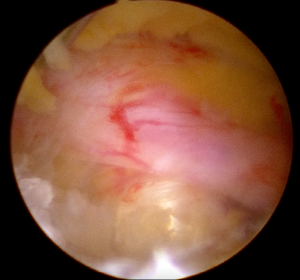

内視鏡画像バイポータル脊椎内視鏡手術は名前の如く、2カ所の小さな切開部(約5~6㎜)から内視鏡と手術器具をそれぞれ挿入して行う手術です。

内視鏡の径はわずか2.7㎜(外套含め3.8㎜)と非常に細く、一方の穴より挿入して内部を観察しながら、もう一方の穴より手術器具を挿入して操作を行います。この内視鏡システムの最大の特徴は、カメラ先端を自由に動かせる点です。従来の内視鏡システムは設置した外套にカメラを固定して行う手術であったために、深部の観察がやや不利でしたが、バイポータル用の脊椎内視鏡はかなり細いカメラのため、これまでの内視鏡では視認が難しかった奥深くまでカメラを挿入し、接近した状態で内部を確認しながら操作することが可能です。これにより、安全性・確実性・低侵襲性が大きく向上しました。手術当日から離床して歩行することはもちろんのこと、術後2~3日で日常生活に復帰できるケースが増えています。

赤枠部分が脊柱管と呼ばれる神経が通る場所です。

術前(左図)ではかなり狭くなっていますが、

術後(右図)では広がって内部の神経や髄液が確認できます。